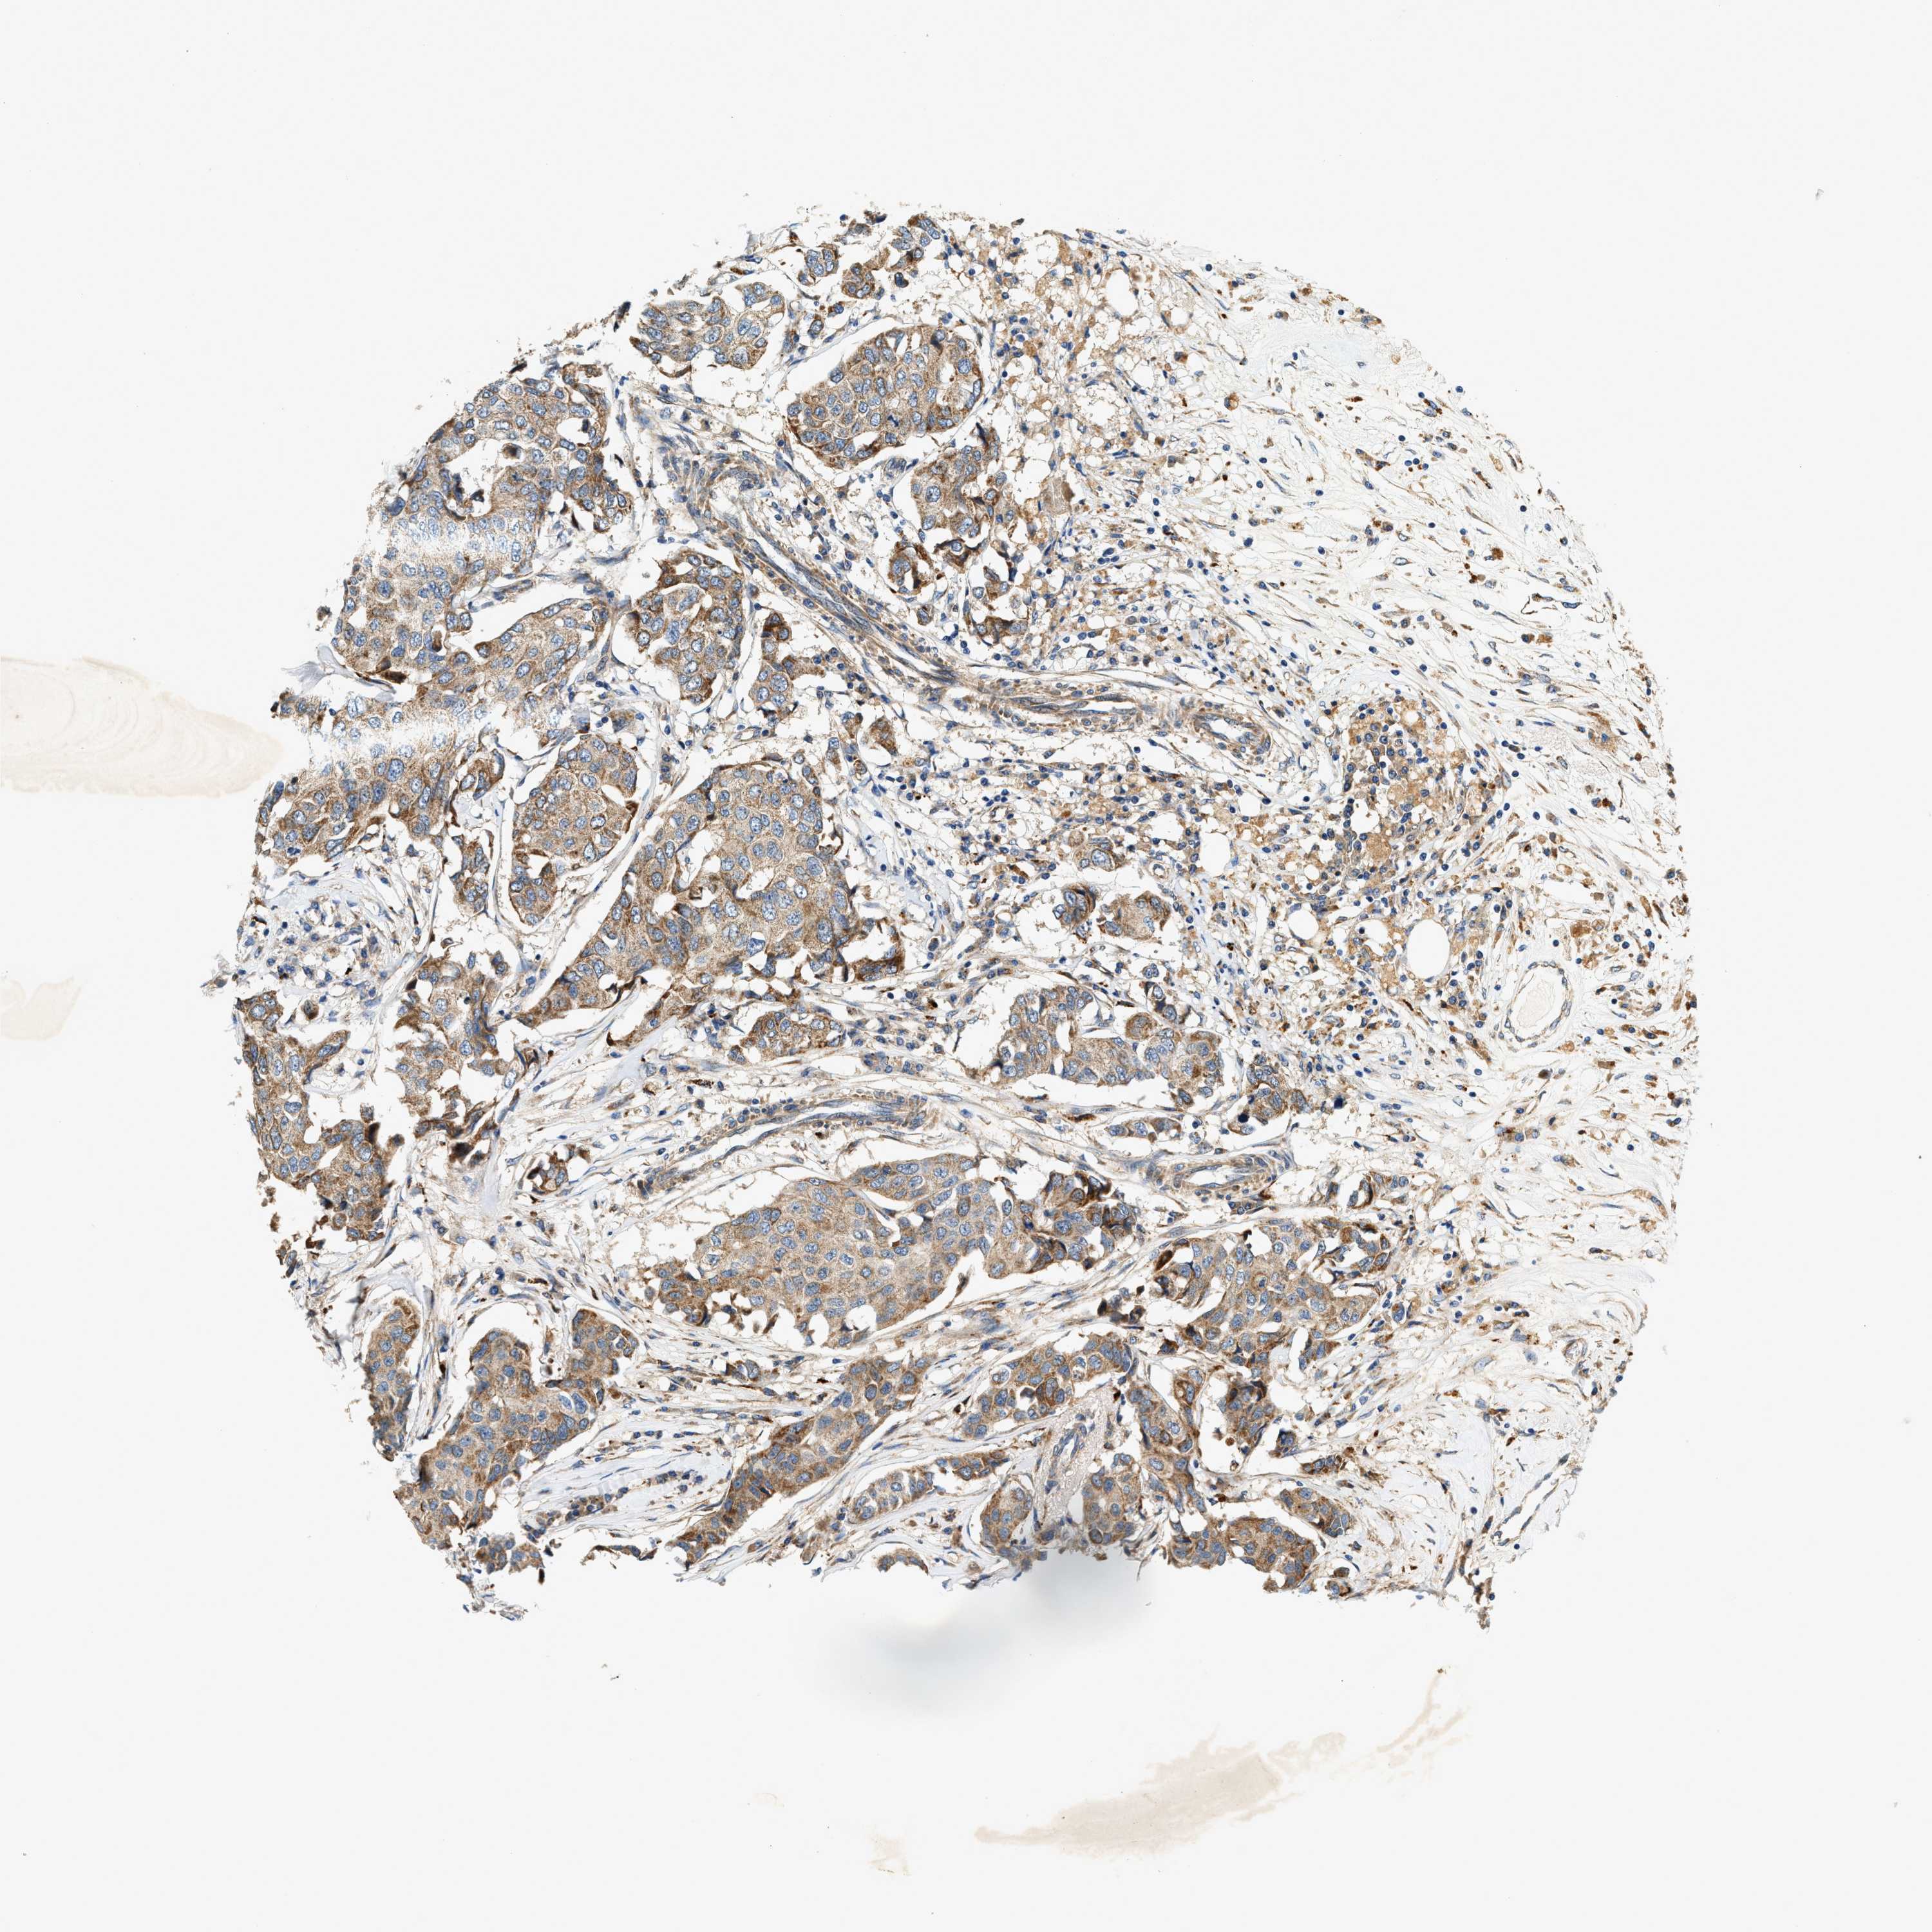

CANCER BREAST CANCER Show tissue menu

BRCA TCGA BRCA VALIDATION PROTEIN EXPRESSION